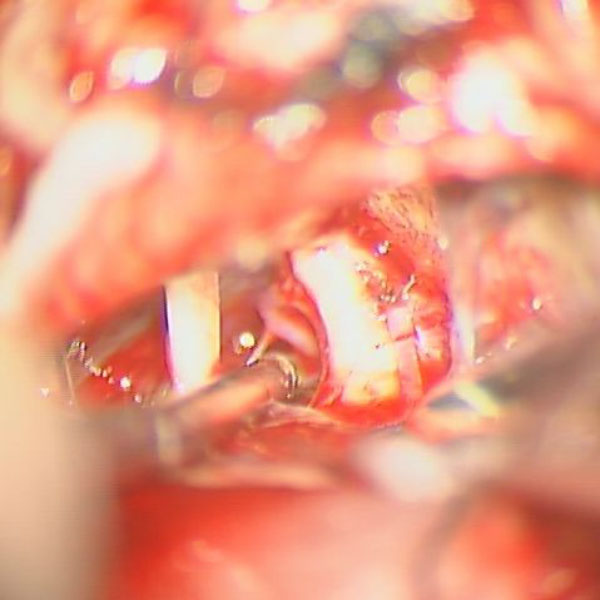

手術中

処置前

処置後